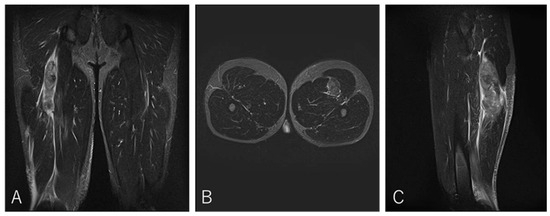

Impact of Proximal Conjoint Tendon Injury on Return to Play in the BF–ST Complex: A Prospective MRI-Based Study

by Makoto Wada, Takumi Okunuki, Takeshi Sugimoto, Yasuhito Tanaka and Tsukasa Kumai

Background/Objectives: Proximal hamstring injuries involving the biceps femoris–semitendinosus (BF–ST) conjoint tendon (CT) often exhibit delayed healing, yet the prognostic significance of CT involvement and intratendinous injury morphology has not been fully clarified. This study aimed to determine whether full-layer CT injury, particularly bilateral [...] Read more.

Background/Objectives: Proximal hamstring injuries involving the biceps femoris–semitendinosus (BF–ST) conjoint tendon (CT) often exhibit delayed healing, yet the prognostic significance of CT involvement and intratendinous injury morphology has not been fully clarified. This study aimed to determine whether full-layer CT injury, particularly bilateral involvement in Zone C, prolongs return-to-play (RTP) in competitive rugby athletes. Methods: This prospective study evaluated 41 university rugby players with acute BF–ST complex injuries using clinical examination, ultrasonography, and MRI. Injuries were classified by Type (I: full-layer CT; II: BFLH-only; III: ST-only), Zone (A–E), and Grade (0–3). RTP was defined as unrestricted return to team training or match play. Group differences were analyzed using ANOVA or non-parametric tests with appropriate post hoc corrections. Results: Type I injuries required significantly longer RTP (11.4 ± 4.8 weeks) than Type II (5.3 ± 2.4 weeks) and Type III (4.0 ± 1.7 weeks), confirming the strong impact of CT involvement on prognosis. In Zone C, bilateral full-layer CT involvement was associated with an approximately twofold longer RTP duration compared with unilateral BFLH-side injuries, indicating that intratendinous tissue disruption influences recovery. These findings highlight the importance of early MRI-based assessment to identify clinically relevant tendon involvement patterns. Conclusions: Full-layer CT injuries, particularly bilateral intratendinous patterns in Zone C, markedly prolong RTP compared with isolated BFLH or ST injuries. An MRI-based classification incorporating injury type, zone, and extent of CT involvement provides clinically valuable prognostic information and may enhance RTP decision-making. Full article

Show Figures

Figure 1